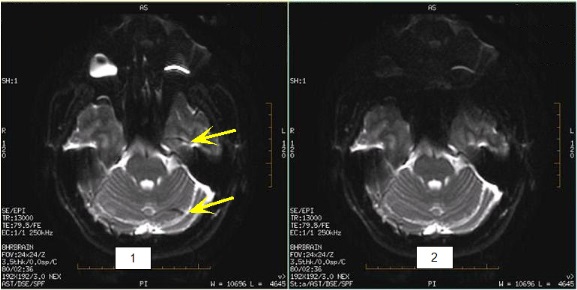

DWI and DTI ring artifact

A ring-like artifact from intense orbit signal can occur on T2-weighted EPI DWI/DTI, ADC/eADC, and Synthetic DWI images.

Position an angled anterior SAT band over the orbits (not the cortex) to suppress the orbit signal intensity and thus minimize the artifact.